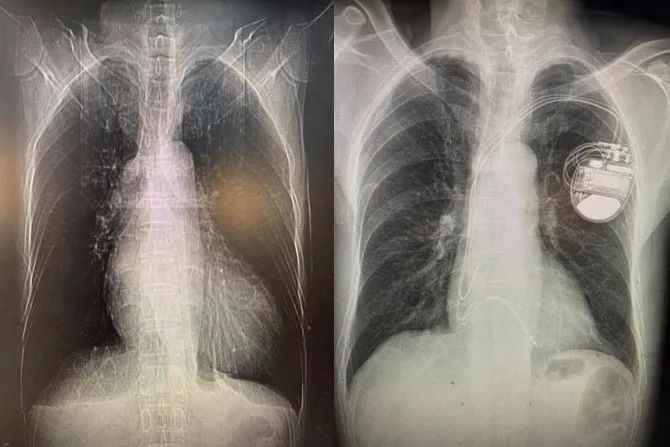

择日,孙冰主任医师和毛玉副主任医师所在的起搏团队为先生进行了起搏器植入手术。张先生植入的起搏器为三腔起搏器,共有三根导线经血管到达心脏,分别位于右心房、右心室和左束支。右心房、右心室得电极保证了心房心室收缩的同步性,并具有防治室速室颤的功能。而左束支电极可以纠正左束支传导阻滞,实现左室内部的收缩同步,改善心功能。经过精细定位和检测,左束支电极植入成功,起搏后可以看到张先生心电图的QRS波迅速变窄,标志左室收缩同步性的达峰时间和胸前导联QRS波移行也非常理想。手术很成功。术后心电图已经看不到原来宽宽的QRS波了,几乎与正常心电图完全一样。这意味着心脏电传导得到了改善,张先生的脸上也露出了笑容。

术前;术后